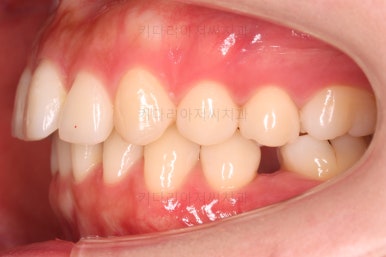

초진 시 입안의 모습인데요.

왜 그런지 비밀이 풀리는 것 같죠?

윗니는 한 쪽이 치아 2개가 결손이면서 유치가 하나 남아있고요.

아랫니는 한 쪽은 1개, 반대편은 2개 치아가 결손이었습니다.

도합 5개의 치아가 결손이었는데요.

결손 위치의 갯수가 위아래 좌우 다 달라서 중앙선이 맞을래야 맞을 수가 없는 상황이었죠.

결손치아 주위 치아들은 쓰러지고 비틀어져 있어서 장기적으로 좋지 못한 상황이었고요.

좀 더 디테일하게 윗니 작은 앞니 1개가 왜소치아라서 치아 크기도 맞지 않은 상황이었습니다.